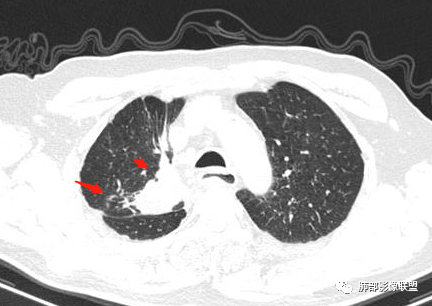

结合本病例,老年男性患者,慢性病程,急性加重,无吸烟史,影像学表现为右肺上叶尖后段斑片实变密度影,整体边界清晰,边缘平直收缩为主,周边散在纤维条索影,内部见支气管内粘液栓,血管影走形正常,没有明显破坏,增强扫描明显强化,缺乏典型分叶毛刺、胸膜改变,病灶也未显示清楚的磨玻璃勾边,病灶大而肺门纵隔未见肿大淋巴结,综合考虑慢性炎性肉芽肿可能性大。但恶性,结核能完全排除吗?我想对临床医生来说还是有很大考验的。